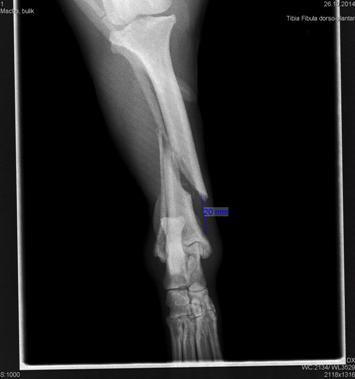

1_Macha_bulik_2